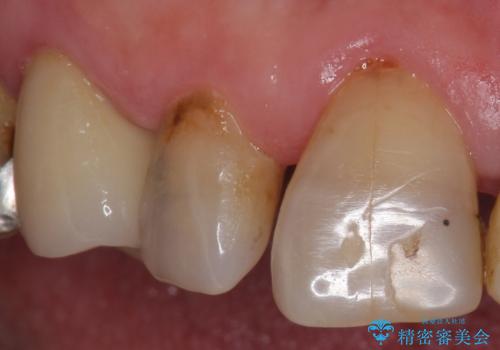

クラウンでの修復は歯の形を変えある程度すき間を埋めることが可能です。

歯と歯の間の大きなすき間と虫歯の両方を解決することができ、大変満足していただけました。